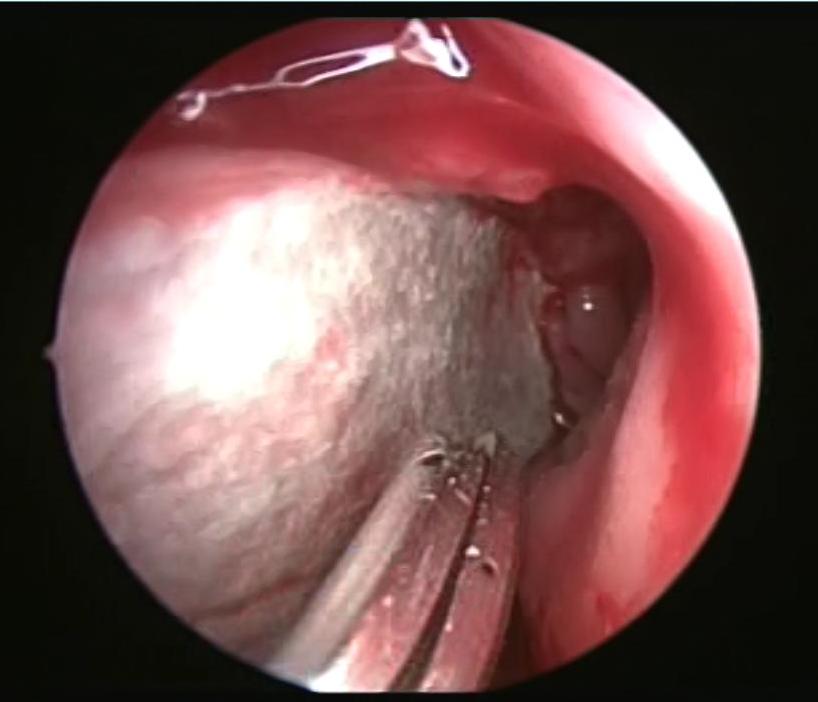

It is an autosomal dominant vascular disorder, which has a variety of clinical manifestations, with epistaxis being one of the most common. Many treatment options exist for epistaxis, but with no consensus on which is the method of choice. We describe the case of a patient with hereditary hemorrhagic telangiectasia (HHT) secondary epistaxis with septoplasty managed with synthetic hard graft, which improved intensity and frequency of bleeding episodes. This technique is a variant of the septodermoplasty described by several authors, but the use of synthetic dura can help in obtaining better results and avoid taking skin grafts from other sites different from the surgical site.